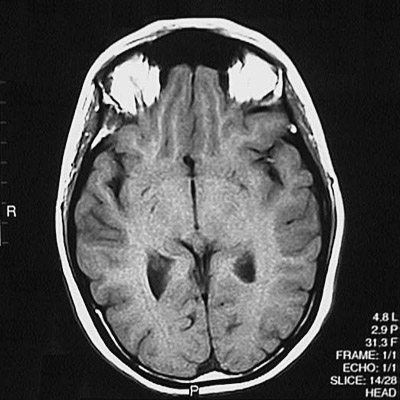

This is a normal axial T1 weighted MRI scan demonstrating the inferior frontal lobe and temporal lobe and occipital lobe and atrium of lateral ventricle and frontal sinus and orbit.